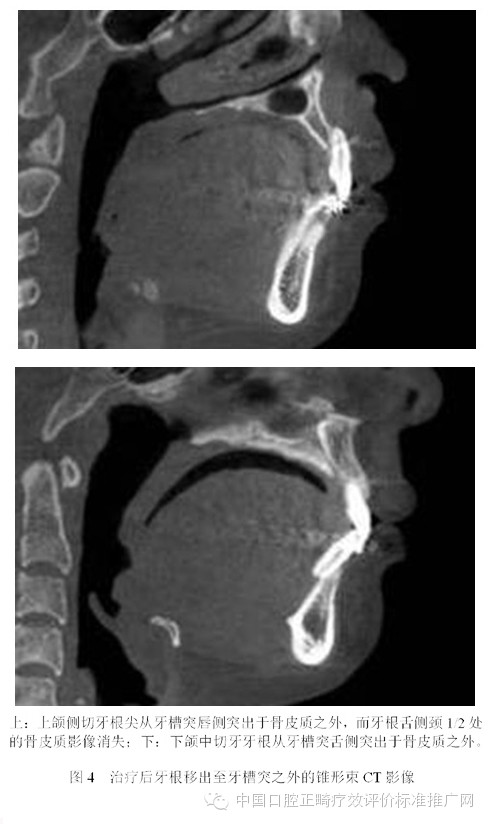

為了避免支抗的丟失,正畸醫(yī)師終于發(fā)現(xiàn)了最強(qiáng)的支抗裝置---金屬種植釘支抗。在用支抗磨牙拉前突的切牙時(shí),切牙牙根在接觸腭側(cè)骨皮質(zhì)后移動(dòng)的阻力會(huì)非常大,于是支抗磨牙會(huì)前移而最終關(guān)閉間隙;但當(dāng)改用種植釘支抗拉前牙時(shí),由于種植釘是絕對(duì)支抗,在矯治力作用下幾乎不動(dòng)[6],因此當(dāng)切牙牙根與腭側(cè)骨皮質(zhì)接觸后,種植釘仍然不會(huì)作任何讓步,那么進(jìn)一步對(duì)抗的結(jié)果會(huì)怎么樣?理想的結(jié)果是腭側(cè)骨皮質(zhì)的牙根一側(cè)發(fā)生骨吸收,而舌側(cè)骨板發(fā)生骨沉積,牙齒帶著牙槽骨一起向腭側(cè)移動(dòng)。問(wèn)題是骨吸收與骨沉積的數(shù)量相等嗎?速度一致嗎?為了回答這個(gè)問(wèn)題,筆者[7]10年前作過(guò)一個(gè)上頜切牙內(nèi)收對(duì)其前后方牙槽骨改建的探索性研究。該研究選擇55例平均年齡為13.3歲的青少年錯(cuò)合患者為研究對(duì)象,采用拔除上下頜第一前磨牙進(jìn)行矯治,平均保持時(shí)間為3年。通過(guò)測(cè)量上切牙阻力中心前方及后方牙槽骨在治療前、治療后及保持后的骨量變化,以及牙槽突總厚度在上述3個(gè)時(shí)間點(diǎn)的變化,結(jié)果發(fā)現(xiàn):上切牙阻力中心在治療后向腭側(cè)平均移動(dòng)了1.8mm (P<0.001);與阻力中心水平的唇側(cè)牙槽骨厚度增加了0.2mm (P<0.01),腭側(cè)牙槽骨厚度減小了0.8mm (P<0.001);隨訪(fǎng)期上切牙阻力中心向唇向復(fù)發(fā)了0.8mm (P<0.01),與阻力中心水平的唇側(cè)牙槽骨厚度相應(yīng)減小了0.2mm (P<0.05),但腭側(cè)牙槽骨厚度卻并沒(méi)有明顯的增加;與上切牙阻力中心水平的牙槽突總厚度基本保持在治療后的水平。由此可見(jiàn),在牙齒移動(dòng)的過(guò)程中,牙槽骨的生物學(xué)改建是以骨吸收為主,骨增生十分有限,即使是保持3年以后,骨增生的量也未達(dá)到其吸收的量。雖然這只是個(gè)初淺的臨床研究,尚有待基礎(chǔ)研究去證實(shí),但它卻部分解釋了正畸臨床上在對(duì)骨性錯(cuò)合患者進(jìn)行牙代償性矯治時(shí),會(huì)出現(xiàn)牙槽骨吸收、裂隙、穿孔,牙齦萎縮或部分根尖移出牙槽骨的現(xiàn)象[8-13]。圖3為1例成人患者在用牙代償性治療方法減少重度深覆蓋深覆合時(shí)出現(xiàn)切牙根尖從舌側(cè)移出牙槽骨的X線(xiàn)影像;圖4為1例采用種植釘支抗大量?jī)?nèi)收上下頜前牙的患者,治療后牙根移出至牙槽突之外的錐形束CT影像。

目前尚不清楚正畸過(guò)程中出現(xiàn)骨開(kāi)窗或骨開(kāi)裂的危害,對(duì)CT影像上牙根突出于骨皮質(zhì)之外多少會(huì)出現(xiàn)有臨床意義的骨開(kāi)窗或骨開(kāi)裂也不得而知,更不清楚由正畸牙移動(dòng)造成的骨開(kāi)窗或骨開(kāi)裂能不能自行修復(fù)。雖然這些問(wèn)題尚無(wú)明確的答案,但是從牙周健康的角度考慮,任何醫(yī)師都沒(méi)有理由相信牙根在牙槽骨之外會(huì)比在它本來(lái)應(yīng)該位于的牙槽突之內(nèi)更加健康。由此可見(jiàn),正畸支抗并非越強(qiáng)越好。70多年以前,正畸學(xué)先驅(qū)Tweed醫(yī)師考慮到牙弓唇頰側(cè)的邊界,提出了拔牙矯治的概念;今天,當(dāng)種植釘支抗風(fēng)靡全球之際,當(dāng)正畸醫(yī)師有能力將前牙無(wú)限內(nèi)收之時(shí),難道不該問(wèn)一句:“牙弓的舌側(cè)有沒(méi)有邊界?”